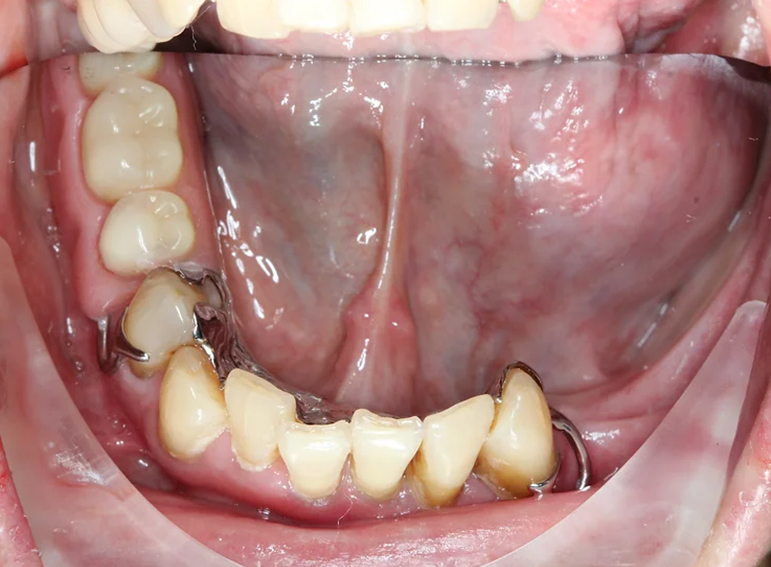

Complex upper and lower denture after oral cancer.